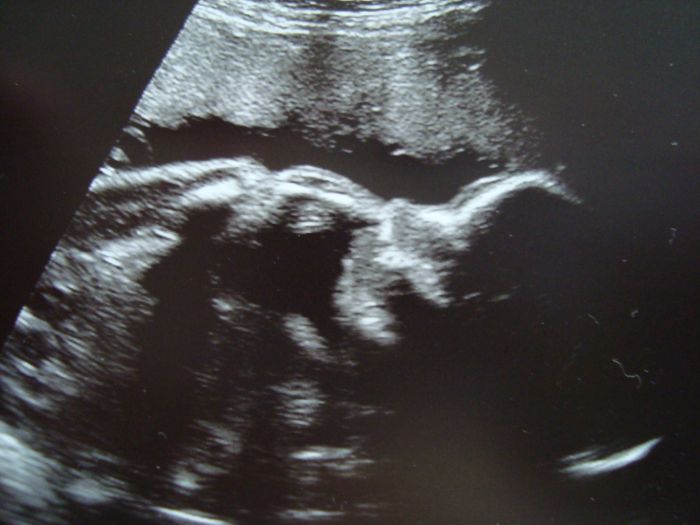

Jeste pokus sem dat fotky naseho Dloubka z minuleho tydne - vrta se prstickem v nose...